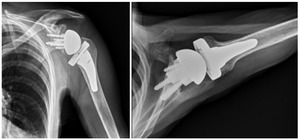

Case four is a 63-year-old retired nurse who was very active with weight lifting, horseback riding, tenis, and yoga. Surgical history included two prior arthroscopid debridements and capsular release. His pre-operative Subjective Shoulder Value (SSV) was 30% and pain score was 10/10. Exam showed 140° of active forward flexion, 30° of active external rotation, and active internal rotation to the sacrum. Radiographs (Figure 11) and CT (Figure 12) scan showed end stage arthritic changes without significant glenoid deformity. Options were discussed with the patient and due to his relatively young age and activity level, an inlay glenoid component was selected. This was combined with mild high side reaming. Radiographs at one year show a well seated component without signs of loosening or failure (Figure 13). Postoperative SSV was 95% and he returned to all prior activities (Figure 14).